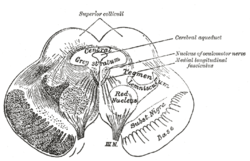

Section through superior colliculus showing path of oculomotor nerve. Periaqueductal grey is the grey area just peripheral to the cerebral aqueduct. | |

Transverse section through mid-brain. 1. Corpora quadrigemina. 2. Cerebral aqueduct. 3. Central gray stratum. 4. Interpeduncular space. 5. Sulcus lateralis. 6. Substantia nigra. 7. Red nucleus of tegmentum. 8. Oculomotor nerve, with 8’, its nucleus of origin. a. Lemniscus (in blue) with a’ the medial lemniscus and a" the lateral lemniscus. b. Medial longitudinal fasciculus. c. Raphé. d. Temporopontine fibers. e. Portion of medial lemniscus, which runs to the lentiform nucleus and insula. f. Cerebrospinal fibers. g. Frontopontine fibers. | |